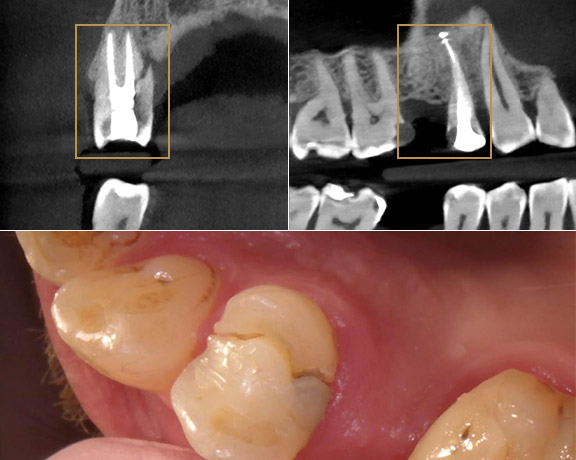

Rola tomografii komputerowej w diagnostyce

Pacjentka zgłosiła się z niewielką plamką na trójce, podejrzewając próchnicę. Ząb był lekko przyciemniony i przebarwiony przydziąsłowo od strony dystalnej. W badaniu nie reagował na test żywotności, co było zaskakujące, bo wcześniej nie był leczony, a podczas rutynowych kontroli nie wykazywał żadnych niepokojących zmian. Lekarz zdecydował o wykonaniu tomografii komputerowej – i dopiero to badanie obnażyło problem. Tomografia wykazała postępujący proces resorpcji (zaciemnienie na zdjęciu), a stopień zniszczenia zęba nie pozostawiał żadnych wątpliwości, co do jego utrzymania.

Rola tomografii komputerowej również w kontroli całości uzębienia - szczęki i żuchwy jest nie do przecenienia. Bardzo często w trakcie takiego badania jesteśmy w stanie zobaczyć zmiany, które podczas rutynowej kontroli są nie do wychwycenia. W tym konkretnym przypadku etiologia resorpcji jest trudna do określenia. Ząb nie miał wypełnień, nie był leczony kanałowo, nie był wybielany, nie było też żadnych zmian w przyzębiu. Pacjentka nie zgłaszała dolegliwości ani urazu zęba.

Pacjent zgłosił się do gabinetu z dużymi dolegliowściami bólowymi. Badanie wykazało konieczność leczenia kanałowego. Zdjęcie rtg (fot. po lewej stronie) pokazuje zmianę okołowierzchołkową, wywołaną stanem zapalnym wewnątrz zęba. Już na pierwszej wizycie udało się udrożnić kanały oraz je wypełnić. Na kolejnej - odbudowano ząb za pomoca nakładu. Zdjęcie kontrolne, wykonane kilka miesięcy po leczeniu (fot. po prawej stronie) pokazuje, że zmiana goi się poprawnie, a Pacjent nie zgłasza żadnych dolegliwości bólowych.